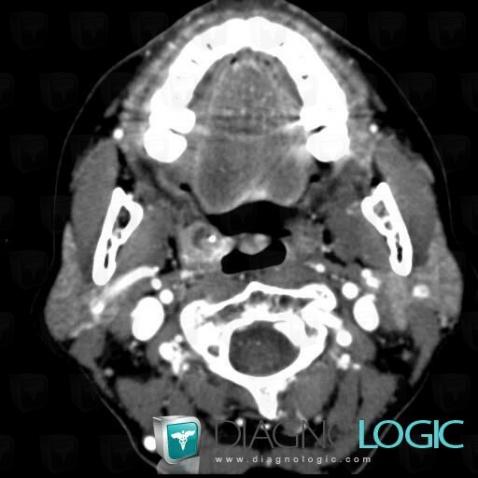

- Diagnostic Cancer de l'amygdale (lié à Cancer oropharyngé), Localisation(s) Oropharynx / Plancher buccal, comportant les gammes Masse non kystique de l'oropharynx ou du plancher buccal

- Diagnostic Métastase (lié à Adénopathie), Localisation(s) Espaces profonds du cou, comportant les gammes Masse kystique cervicale

- Diagnostic Métastase, Localisation(s) Espaces profonds du cou, comportant les gammes Adénomégalie cervicale, Adénomégalie cervicale hypodense à réhaussement périphérique